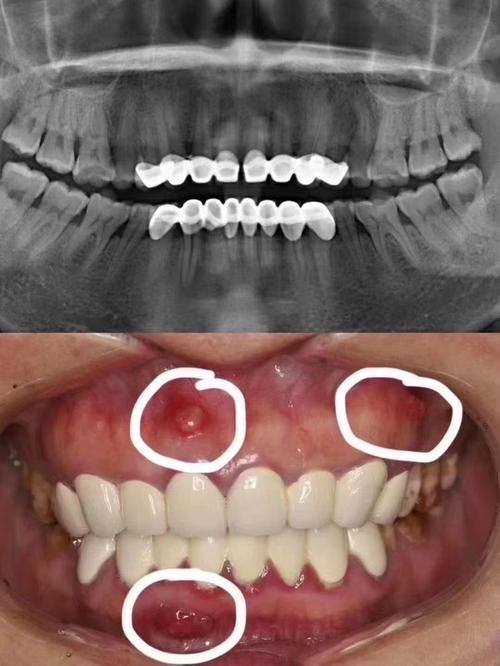

部分早期使用的烤瓷牙可能含有铁磁性金属。这类材质在强磁场环境中就像一个调皮的孩子,可能会发生位移或产热。所以,如果你的烤瓷牙是早期安装的,更好提前通过口腔X光片确认一下材质,这样才能确保检查的安心。

对于植牙患者来说,情况又有所不同。钛合金种植体与核磁共振的兼容性良好,就像一对默契的伙伴,可以在磁场环境中和谐共处。但是,附着在钛合金种植体上的金属烤瓷冠仍需谨慎评估。因为金属烤瓷冠的内冠材料可能会对核磁共振检查产生影响,所以在进行检查前,一定要向医生详细说明情况,让医生进行专精的评估。